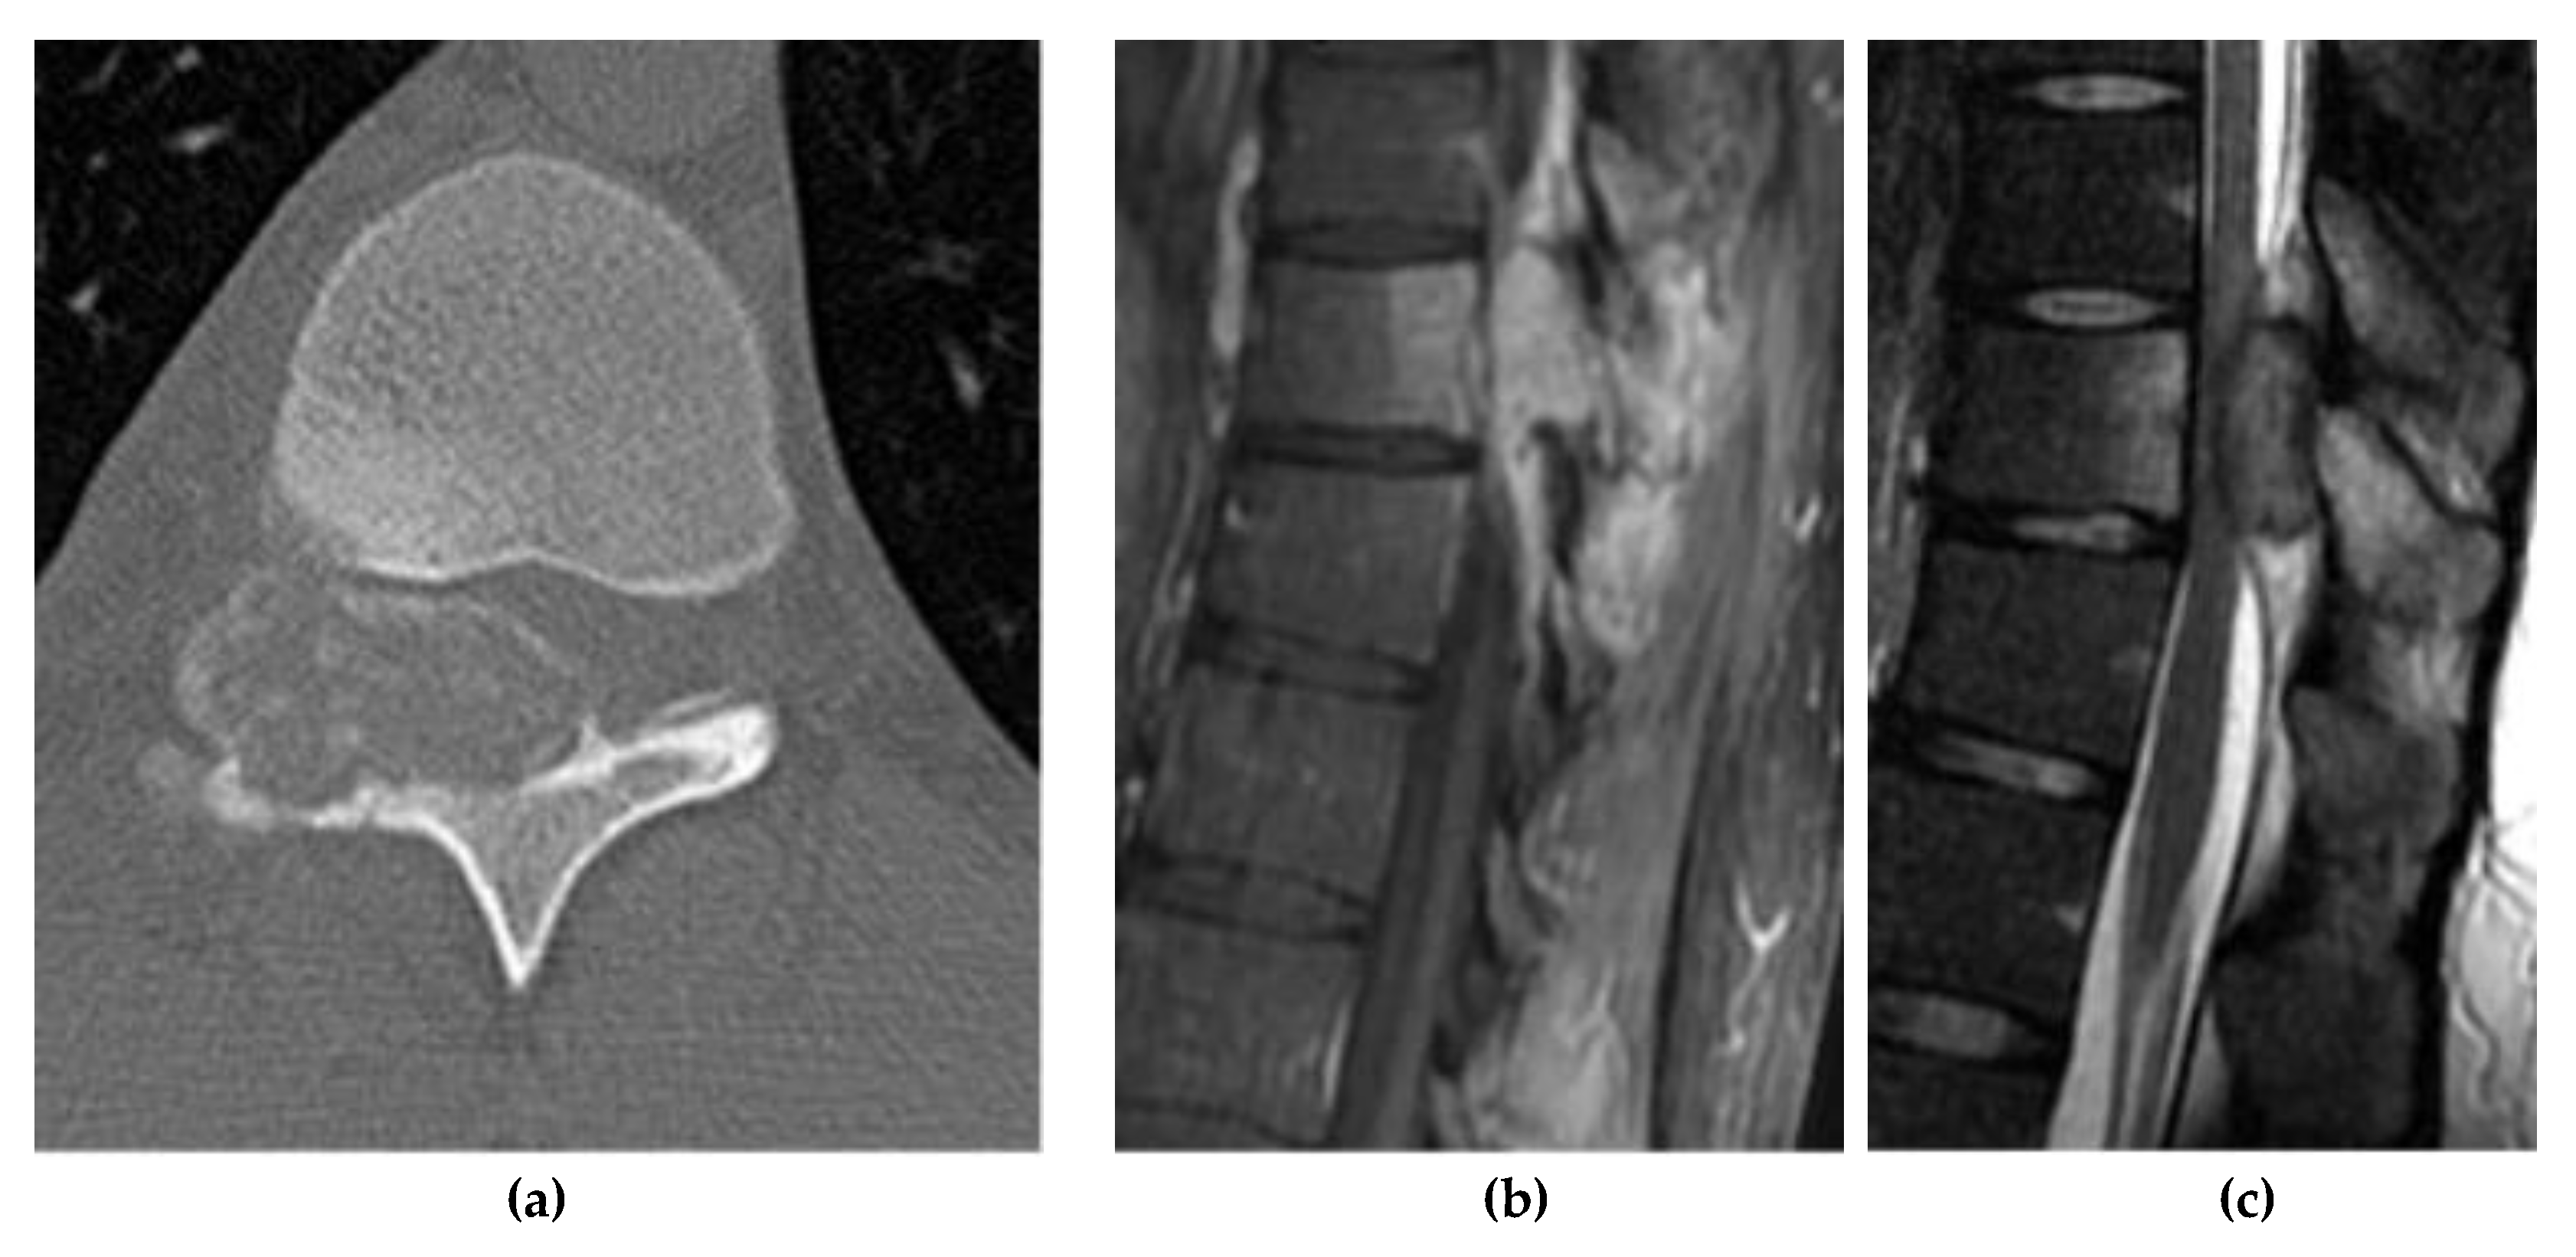

Giant Cell Tumor

8. Adipocytic